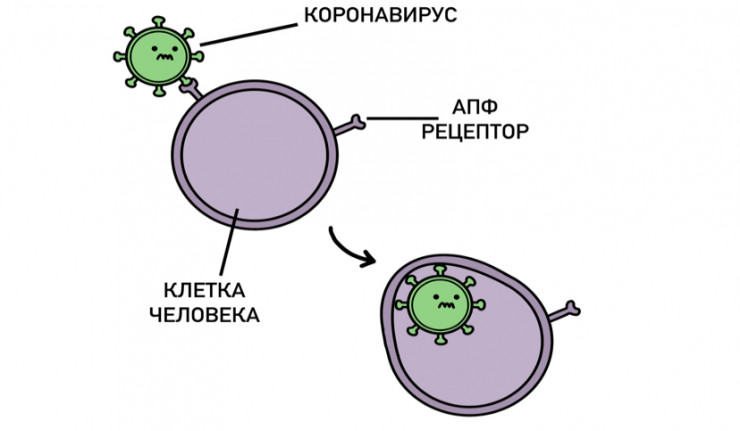

Болезнь начинается с момента, когда коронавирус попадает в организм через дыхательные пути и начинает там размножаться. Для этого он должен с помощью своих шипов прикрепиться к так называемым АПФ-рецепторам, которых много у пожилых людей и у тех, кто страдает хроническими болезнями.